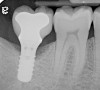

Fig 4. A radiograph of the area suggests the advanced nature of this lesion.

Figure 4